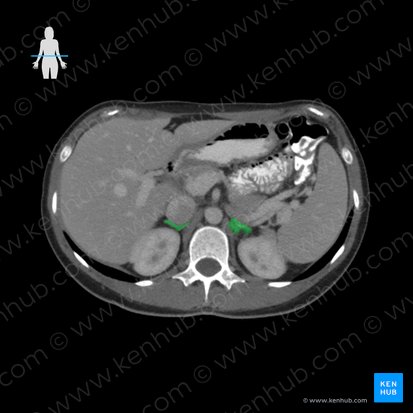

Schließlich sollten auf dem CT auch immer die großen Blutgefäße des Abdomens beurteilt werden. Zu diesen gehören die Aorta abdominalis und die Vena cava inferior. Die Aorta abdomianlis verläuft im Retroperitonealraum. Sie tritt durch den Hiatus aorticus des Zwerchfells (Th12) hindurch und steigt anterior der Wirbelsäule ab. Die Aorta abdominalis teilt sich auf Höhe des Vierten Lendenwirbels in zwei Endäste – die rechte und die linke Arteria iliaca communis. Die Vena cava inferior befindet sich rechts der Aorta. Sie entsteht durch die Vereinigung der beiden Vv. Iliacae communes auf Höhe des Fünften Lendenwirbels und tritt durch das Foramen venae cavae des Zwerchfells (T8) hindurch.

In erster Linie sollte der Durchmesser der Blutgefäße abgeschätzt werden. Eine Erweiterung kann auf ein Aneurysma der Bauchaorta hindeuten. Eine Vergrößerung des Durchmessers der Vena cava inferior ist mit einem erhöhten Thromboserisiko assoziiert.